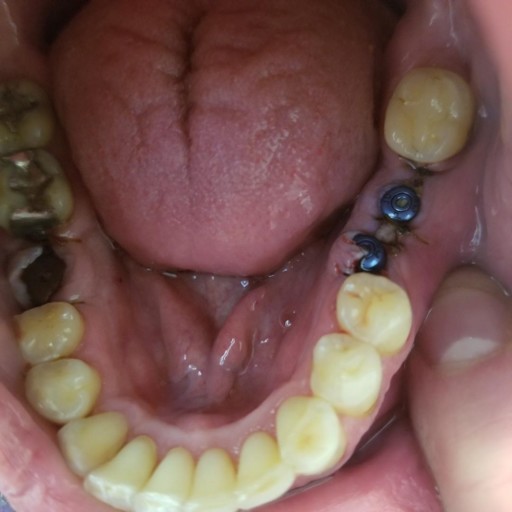

Two weeks ago i had an implant put in my mouth on the right side of my lower jaw. Unfortunately my dentist drilled to far with the implant drill and nicked the Inferior alveolar nerve which provide sensation to my lower lip, chin as well as gums and teeth. It took me a week just to come to terms with. I'm trying to remain hopeful but its hard. this. My dentist informed me that nerves heal slow and this might take weeks months or even a year. He cant even guarantee ill ever get feeling back. The tightness in my lower right teeth are the hardest thing to deal with right now. Its feels like a have toothpicks stuck between each of them. My current dilemma is trying to decide whether or not to remove the existing implant that he was then able to install. We confirmed the next day by 3d scan that the implant he installed is not near the nerve canal so his feeling was to leave it in.

I would rather leave it in and not risk causing more damage to an already injured nerve. Now the confusing part is when i got a second opinion from a different dentist he advised me to take the implant out. My question is if its not violating the nerve canal what is the harm in leaving it in? He acknowledge that there is no physical impingement to the nerve from the implant but wont elaborate further about why to remove it. I just want to make sure i give myself every opportunity to heal. I just dont know whether to leave it in or take it out. Also is there a type of doctor that specializes in this type of thing? Possibly a neurologist? Any suggestion or any other healing tips or protocol in this type of situation would be greatly appreciated. Thanks Mike